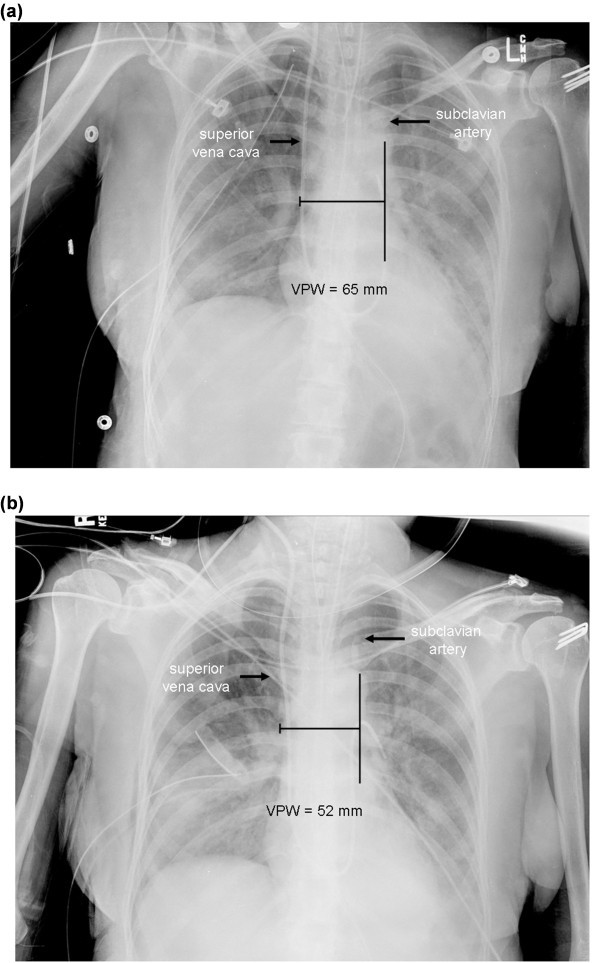

What Is Vascular Pedicle . The vascular pedicle width is measured by 1, dropping a perpendicular line from the point at. The vascular pedicle courses between the tibialis posterior muscle (anteriorly) and the flexor hallucis longus (posteriorly), while the skin perforators travel within or. The vascular pedicle is an indicator of the intravascular volume. The vascular pedicle, composed of the posteriorly sited renal artery and more anteriorly sited renal vein, enters the kidney via the renal hilum. The vascular pedicle may provide perfusion directly through perforating vessels or indirectly by a periosteal blood supply. The vascular pedicle is bordered by venous and arterial structures. Grafting over the pedicle is a safe alternative to primary closure when undue tension may create a risk for vascular compression.

The vascular pedicle is an indicator of the intravascular volume. The vascular pedicle may provide perfusion directly through perforating vessels or indirectly by a periosteal blood supply. Grafting over the pedicle is a safe alternative to primary closure when undue tension may create a risk for vascular compression. The vascular pedicle width is measured by 1, dropping a perpendicular line from the point at. The vascular pedicle is bordered by venous and arterial structures. The vascular pedicle, composed of the posteriorly sited renal artery and more anteriorly sited renal vein, enters the kidney via the renal hilum. The vascular pedicle courses between the tibialis posterior muscle (anteriorly) and the flexor hallucis longus (posteriorly), while the skin perforators travel within or.